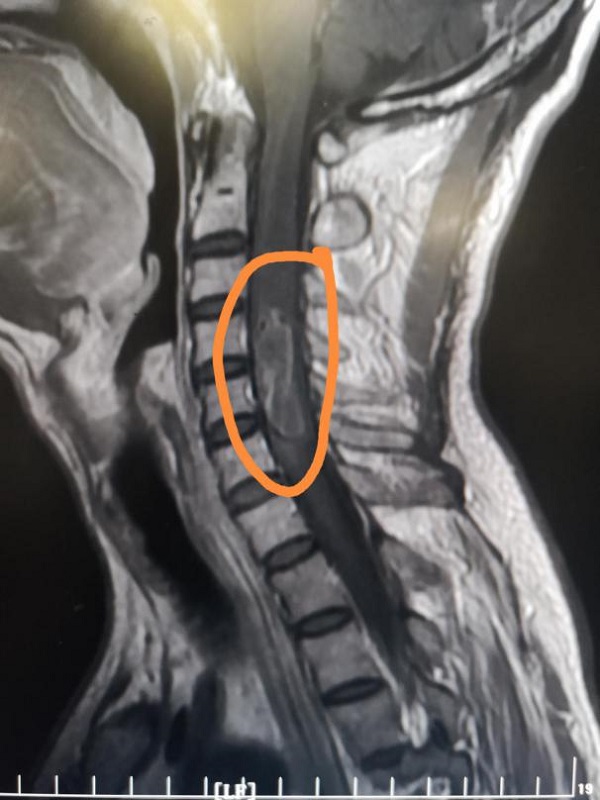

术前磁共振显示:患者颈4-6水平髓内大小为3.4cmx0.9cm异常强化灶

术后肿瘤复查显示肿瘤已完整切除,脊髓内残腔明显缩小。